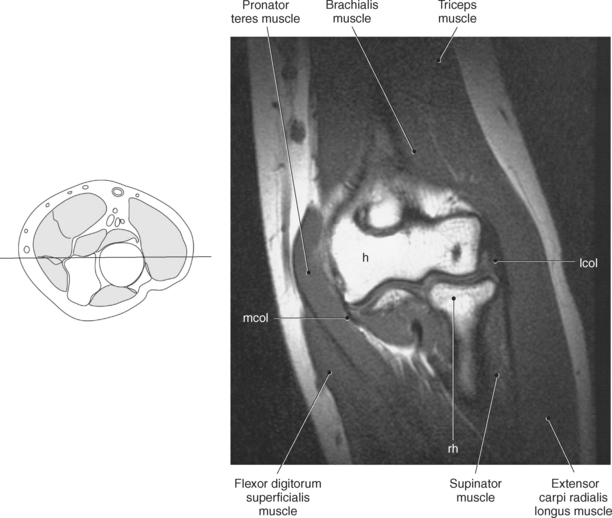

Figure 9.71 Coronal T1-weighted MR scan of elbow.

Key: ol, Olecranon fossa; me, medial epicondyle; tro, trochlea; le, lateral epicondyle; cap, capitellum; rh, radial head; rt, radial tuberosity; rn, radial notch; corn, coronoid process.

The distal portion of the humerus has two distinct prominences termed the medial and lateral condyles, with associated epicondyles, that provide attachment sites for tendons and ligaments (Figure 9.70). The medial epicondyle serves as the site of origin for the common flexor tendon, pronator teres muscle, and medial collateral ligament, whereas the lateral epicondyle serves as the attachment site for the common extensor tendon, supinator muscle, and lateral collateral ligament. Just lateral to the medial epicondyle along its posterior surface is a shallow groove containing the ulnar nerve. Two depressions located on the distal humerus are the anterior coronoid fossa and the deep posterior olecranon fossa. These depressions accommodate the coronoid and olecranon processes of the proximal ulna (Figures 9.70, 9.71, and 9.73). The distal humerus has two cartilage-covered articular surfaces—the capitellum and the trochlea for articulation with the radius and ulna (Figure 9.71). The lateral of the two surfaces is the capitellum, a rounded projection that articulates with the concave surface of the radial head. The trochlea is more medial and has the appearance of an hourglass if viewed in the horizontal plane. The shape of the trochlea helps keep the ulna in position during flexion between the distal humerus and proximal radius (Figure 9.73).